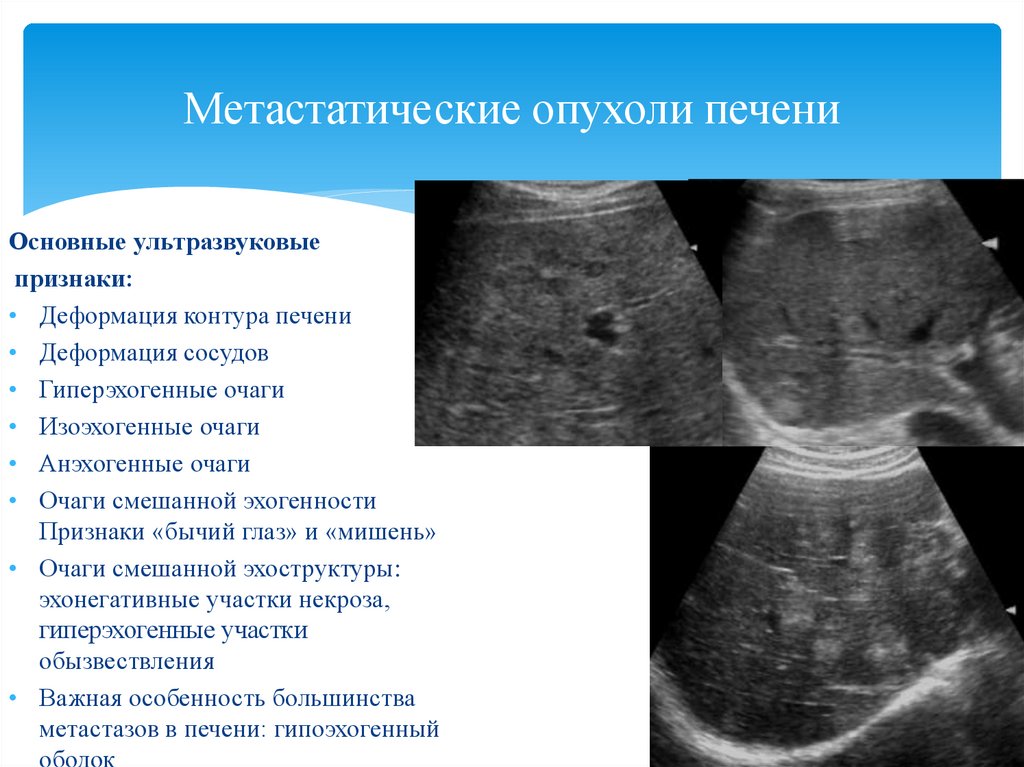

Метастатические поражения печени в ультразвуковом изображении характеризуются